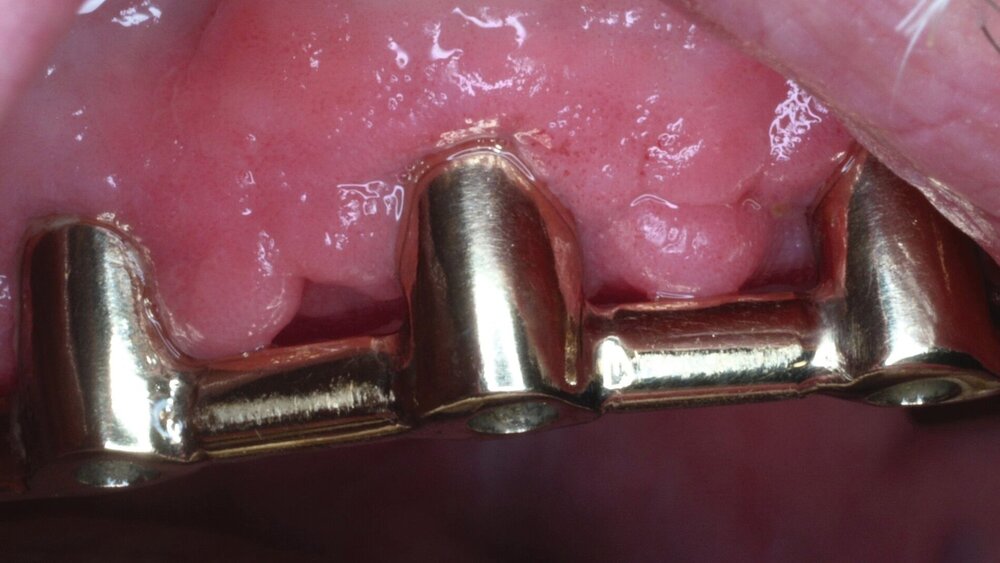

„Pflegebedürftige und Menschen mit Behinderungen können oft nicht mehr eigenverantwortlich für ihre Mundhygiene sorgen, die im Schnitt schlechter als die der übrigen Bevölkerung ist", betont Martin Hendges, Vorsitzender des Vorstandes der KZBV.

"Das Risiko für Karies-, Parodontal- und Mundschleimhauterkrankungen ist bei diesen Patienten besonders hoch. Daher ist es umso wichtiger, sie regelmäßig und zielgruppenspezifisch zahnmedizinisch zu versorgen. Speziell für ihre Bedarfe haben wir zugeschnittene Versorgungskonzepte entwickelt; das Leistungsspektrum wurde in den vergangenen Jahren erheblich erweitert. Die jetzt vorliegenden Daten zeigen den Erfolg und die Notwendigkeit dieses wichtigen Versorgungsangebots.“